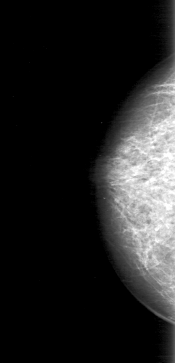

D_4038_1.RIGHT_MLO

RIGHT_CC LINES 5071 PIXELS_PER_LINE 2446 BITS_PER_PIXEL 12 RESOLUTION 43.5 NON_OVERLAY

RIGHT_MLO LINES 5266 PIXELS_PER_LINE 2326 BITS_PER_PIXEL 12 RESOLUTION 43.5 NON_OVERLAY